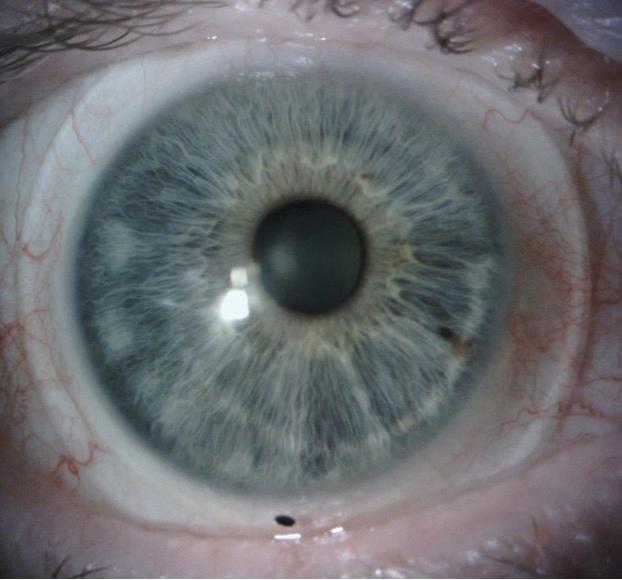

At the second lens dispense and follow up, the patient achieved clear and single vision with the 4 pd BD lens OD (Figure 2, Figure 3). The prism was then split into 2 pd base down OD and 2 base up OS to achieve a thinner lens thickness OD from 0.54 mm to 0.38 mm. The vertical landing zone was also steepened to assist in lens centration and rotational stability. The gas permeability of the lens was increased from 100 to 180 as well to compensate for the reduction in oxygen transmittance due to increased lens thickness from the incorporation of prism.

The patient achieved clear, single vision and a rotationally stable and acceptable fit with the final dispensed scleral lenses. The final lens parameters for the OD lens were a diameter of 16.8 mm, a base curve of 8.04 mm, a sag of 5.157 mm, with a power of -5.25 D. Center thickness was 0.38 mm, the flat scleral landing zone was 3.00, and the steep landing zone was -6.00 with 2 pd BD. For the left eye, the diameter meas-ured 16.8 mm, the base curve was 8.04 mm, with a sag of 5.158 mm, with a power of -5.50D, a center thickness of 0.37 mm, a flat scleral landing zone of 3.00, and a steep landing zone of -6.00, with 2 pd BU. The final lens material for both lenses was tisilfocon A OU. Final scleral lens acuities were 20/20 OD, OS, OU with single and binocular vision.